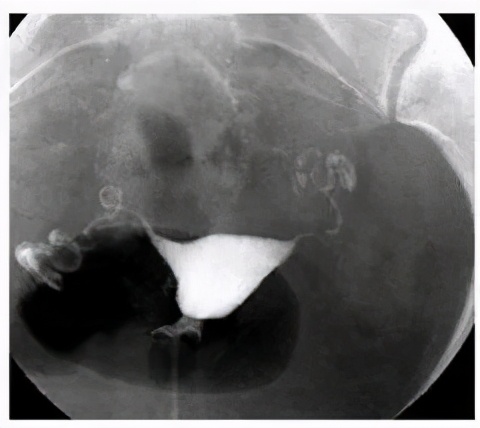

子宫输卵管造影是将碘造影剂直接由子宫颈管注入子宫腔,再经子宫腔到输卵管,在X线透视下了解子宫腔和输卵管腔畅通情况。此检查客观直接,是有效的输卵管检查方法。

输卵管通液和造影是两种不同的检查方法。输卵管通水属于凭手感或是仪器数据显示,间接判断输卵管通或是不通,虽然也可以起到一定的治疗作用,但不够直观;造影则可以直观地通过拍片,看出阻塞的具体部位及程度,因此,从诊断方面来说,造影的效果比通水好得多。